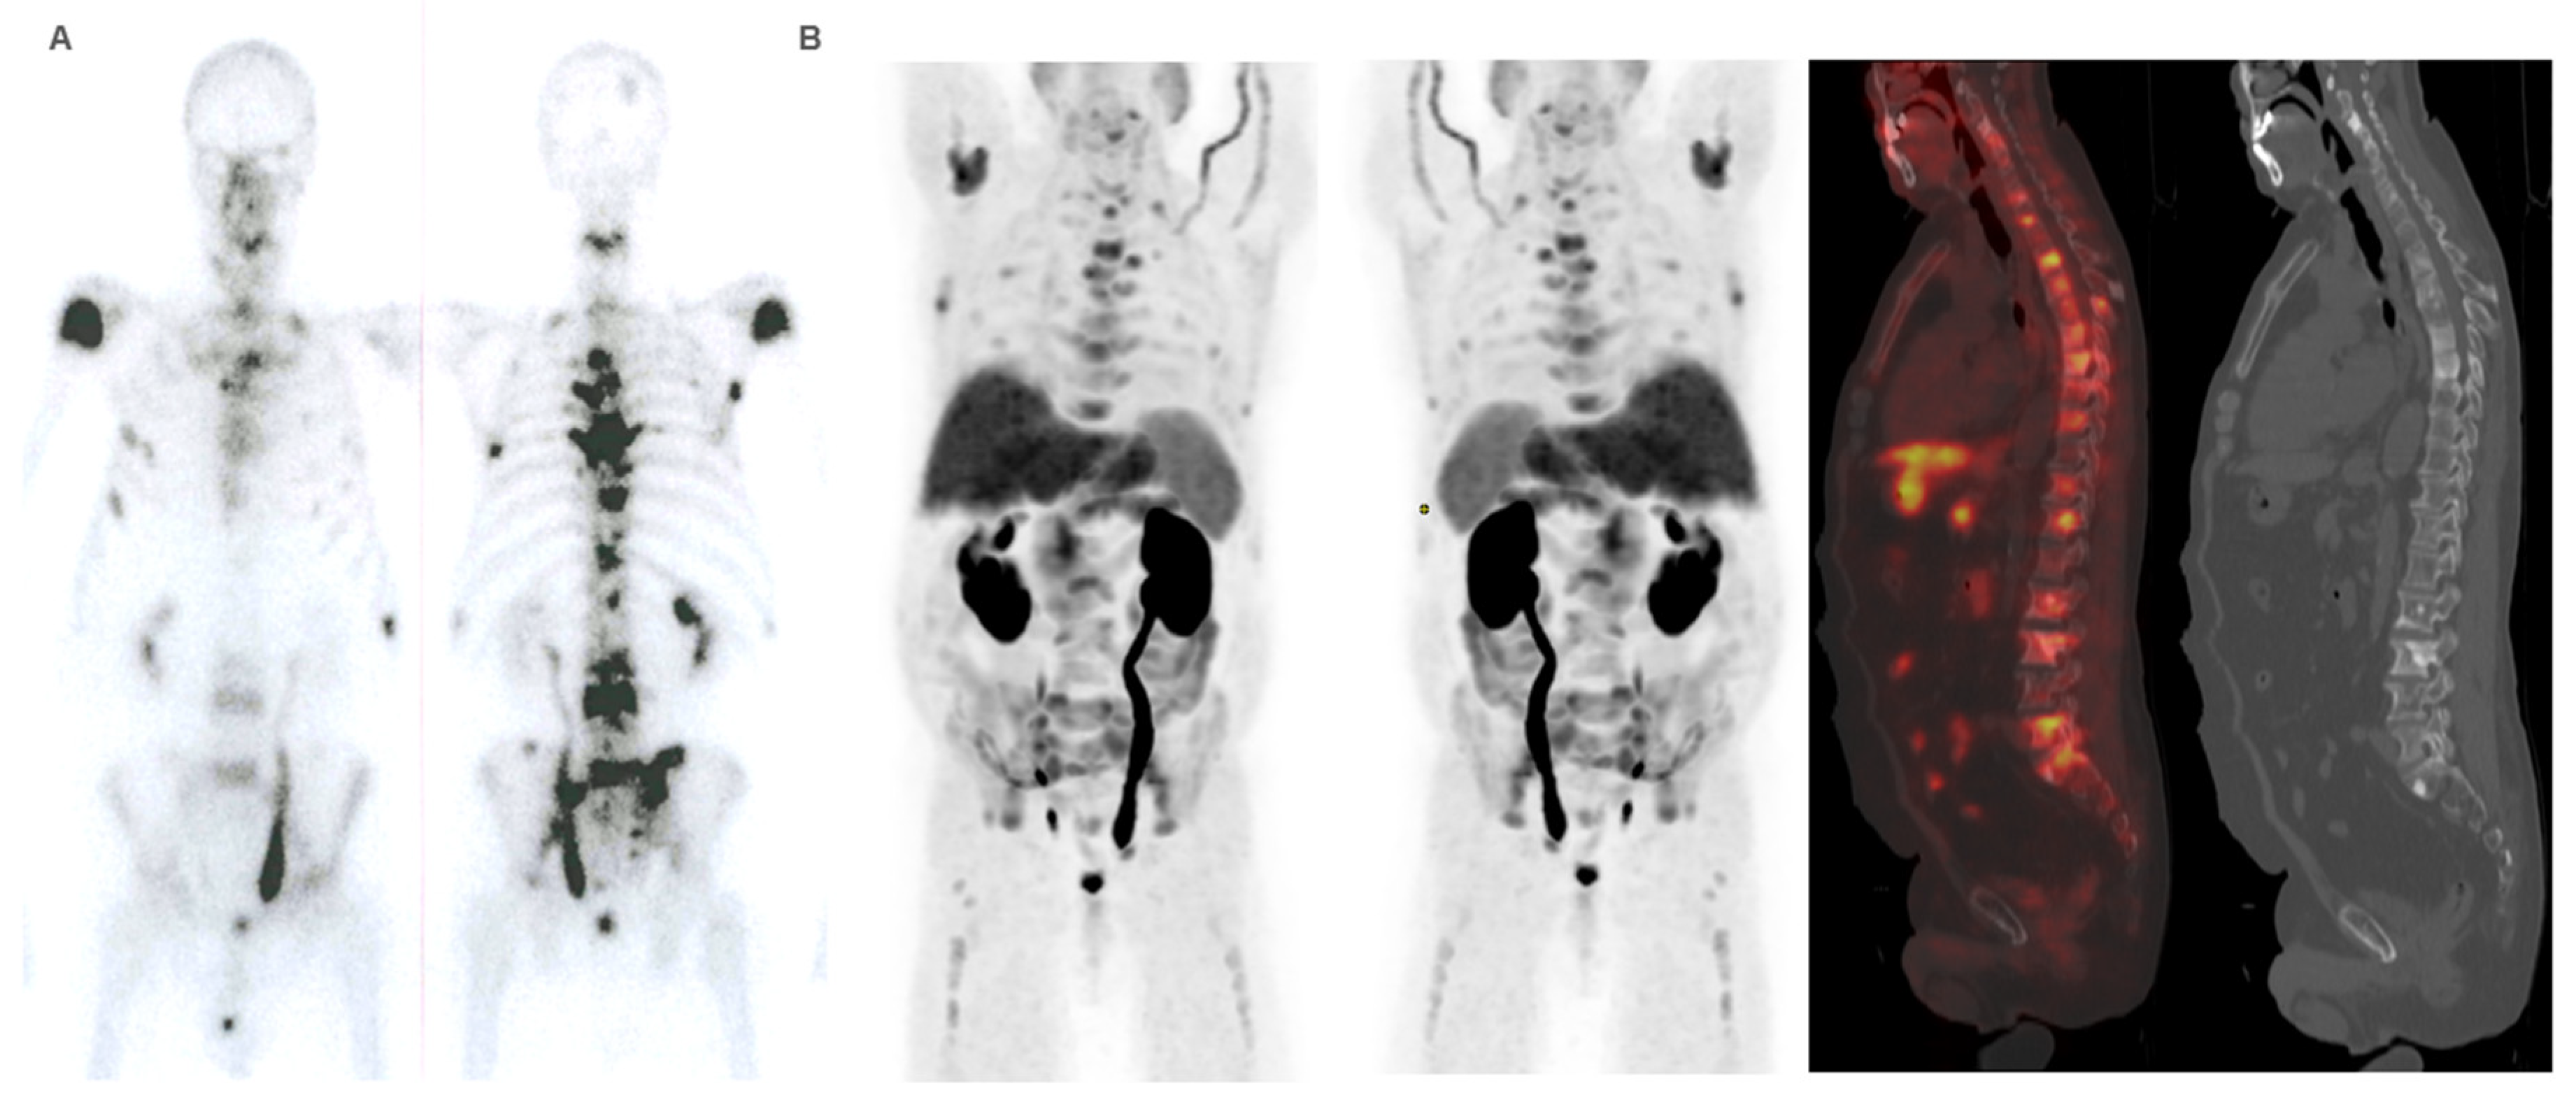

Diagnostic Imaging in Patient Selection

Response Assessment